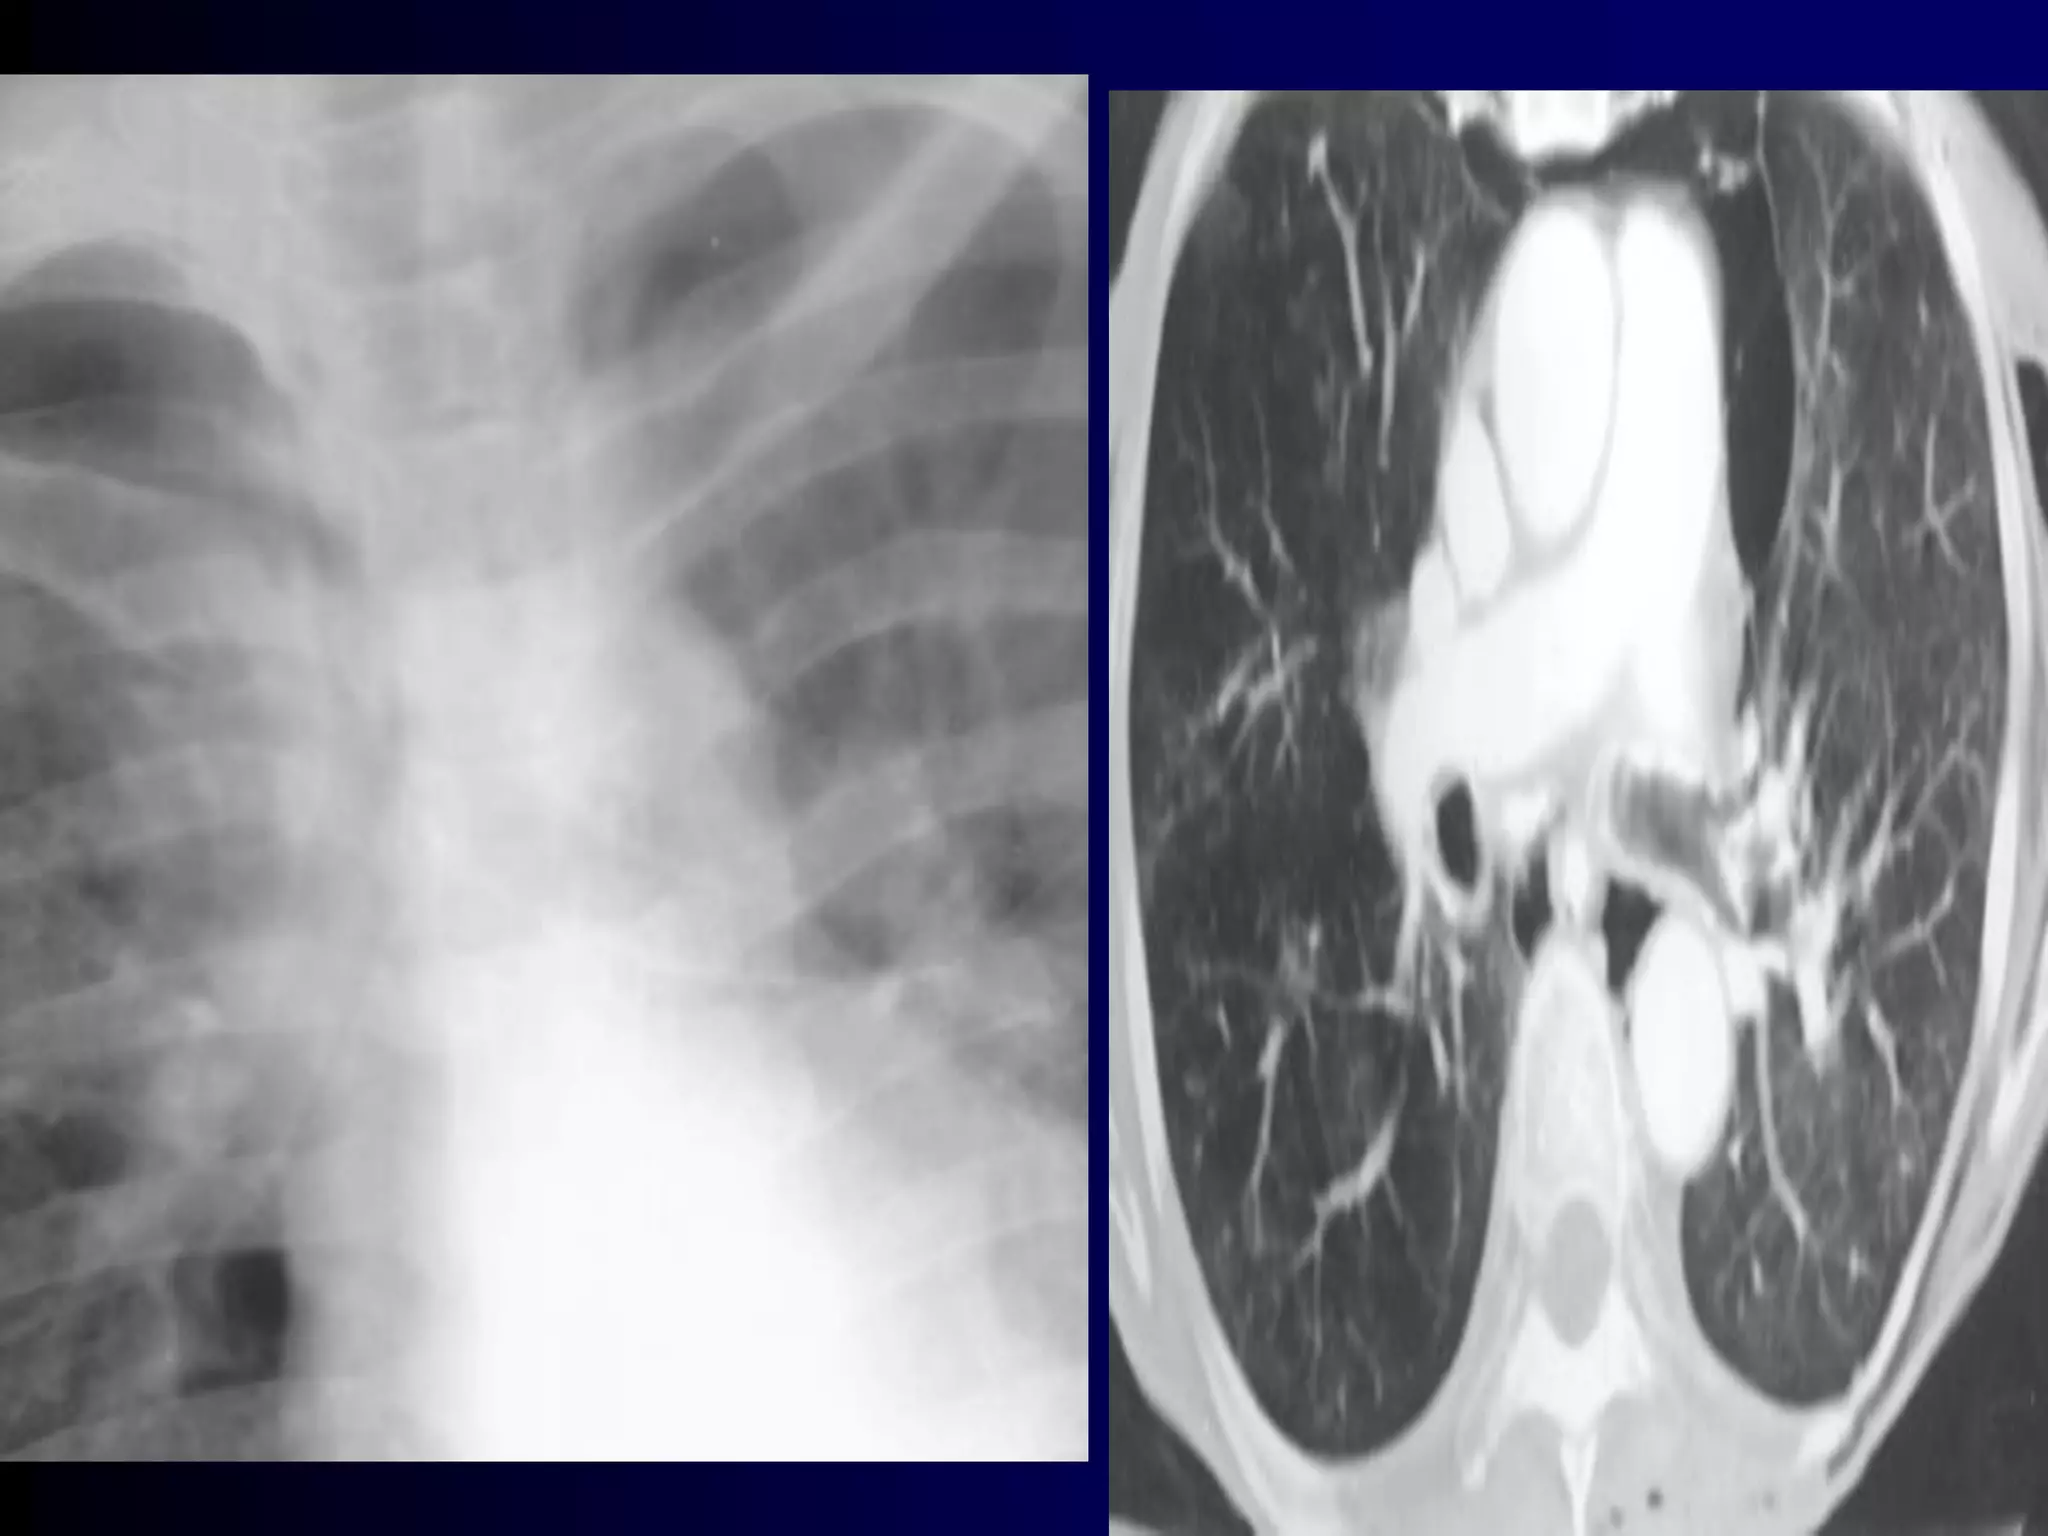

A 46 year old man comes to your clinic for management of

Sputum culture is negative. IgE level is 3,600 ng/mL. His

primary doctor obtained imaging and a chest CT, which

are shown.

Allergic bronchopulmonary aspergillosis (ABPA) is an

ongoing hypersensitivity reaction in response to

Diagnosis:

By constellation of symptoms and objective

findings. "Classic" ABPA would include the

following:

Asthma history

Immediate reactivity on skin prick with Aspergillus

antigens

Precipitating serum antibodies to A. fumigatus

Serum total IgE concentration >1,000 ng/mL

Peripheral blood eosinophilia >500/mm3

Lung opacities on chest x-ray or chest HRCT

Central bronchiectasis present on chest CT

Elevated specific serum IgE and IgG to A.

fumigatus

A skin test is the best first test, as it

is considered 100% sensitive (i.e., a

negative test rules out the condition).

A serum IgE < 1,000 or negative

precipitating antibodies also rule out

ABPA with high confidence.